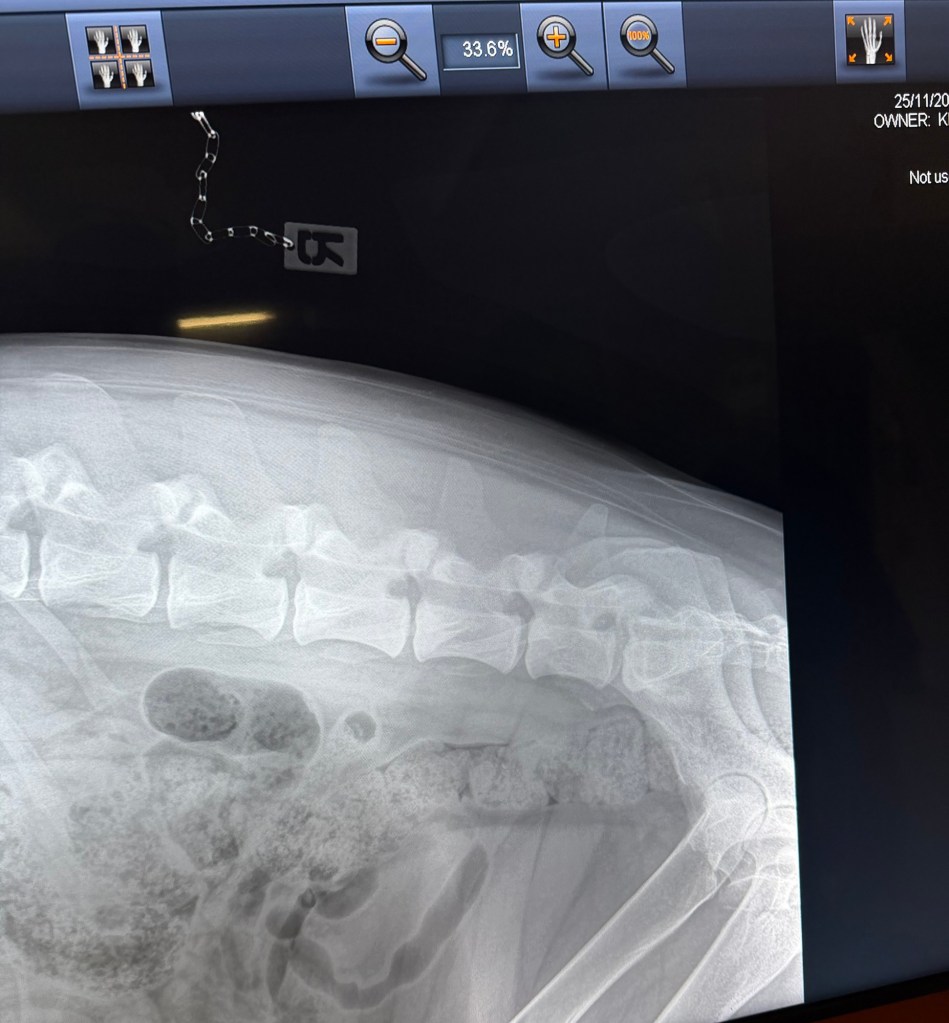

Geri var på ny røntgen nå i november 2025, i en alder av 3år og 8måneder. Dette for å være ansvarlig og forsikre meg om at det ikke blir avl på foreldredyr som har feil utvikling og avdekke svakheter hvis de eksisterer.

Det viste seg å være meget positive resultater (legger ved noen av bildene). Ingen forkalkninger og fremdeles fine albuer, ingen forandring fra 18 måneder HD/AD røntgen til nesten 4års alder. Hun har også en meget fin rygg, og spesielt god og robust lenderygg (bak) som er et fokus område for schæferhunden.